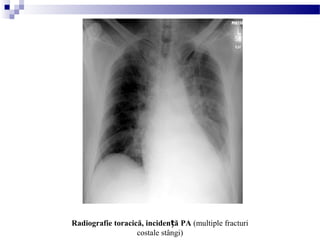

Radiografie toracică, inciden ăț PA (multiple fracturi

costale stângi)